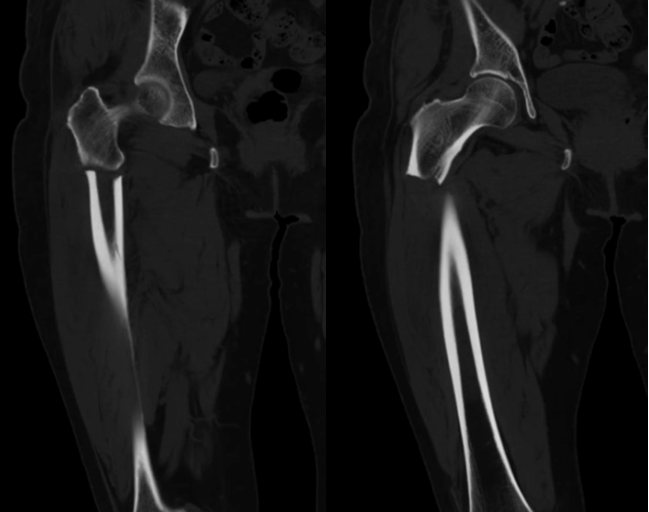

經(jīng)進一步了解,得知老人6年前曾因摔傷致“右橈骨遠端骨折”進行手術治療,住院期間確診為重度骨質疏松,出院后一直應用雙膦酸鹽藥物抗骨質疏松。本次輕微活動后即出現(xiàn)骨折,住院后通過綜合病史、查體、檢查、檢驗等綜合評估,診斷為長期應用雙膦酸鹽類藥物出現(xiàn)的一種特殊類型骨折:非典型骨折(股骨),患者隨后進行手術治療。

CT冠狀位

非典型股骨骨折是由長期服用雙磷酸鹽藥物導致的股骨干部骨折,其特點與創(chuàng)傷性股骨干骨折完全不同。骨折好發(fā)部位:骨折位于股骨干部,股骨小轉子以下,股骨髁以上。